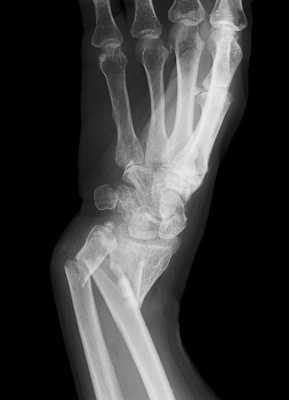

If you have suffered a fracture, you are probably itching to get it healed as soon as possible. Ultimately, it takes time for the bone to fully, and properly, repair itself. But, there are many things you can do to optimize the process and encourage a speedier recovery. Here are just a few tips to get you started on the road to recovery: